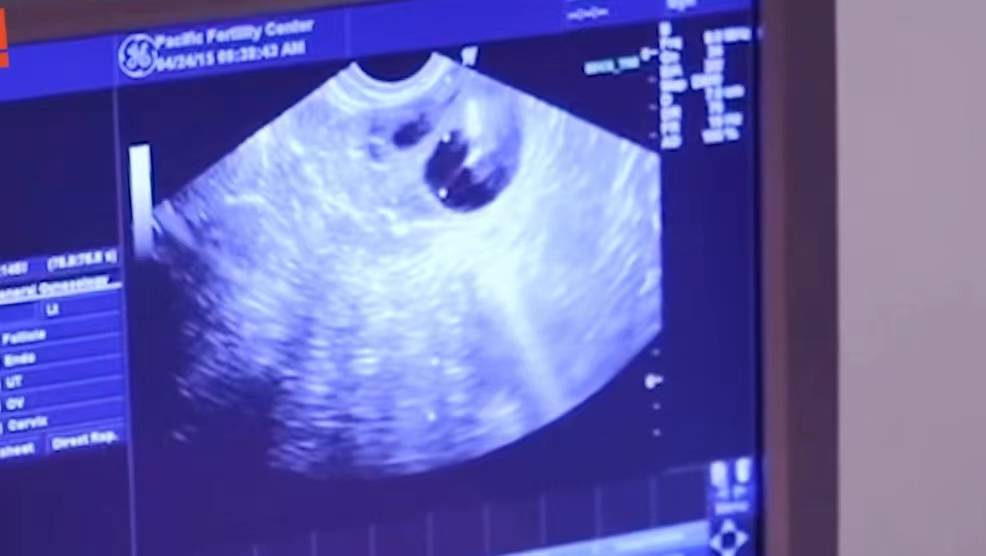

叶海洋亲眼看着胚胎植入自己的子宫 。

文章图片

看到胚胎植入体内 , 她眼眶湿润了 , 感觉到一个生命的力量 , 她变得小心翼翼 , 不敢大踏步走路:“担心她掉出来 。 ”